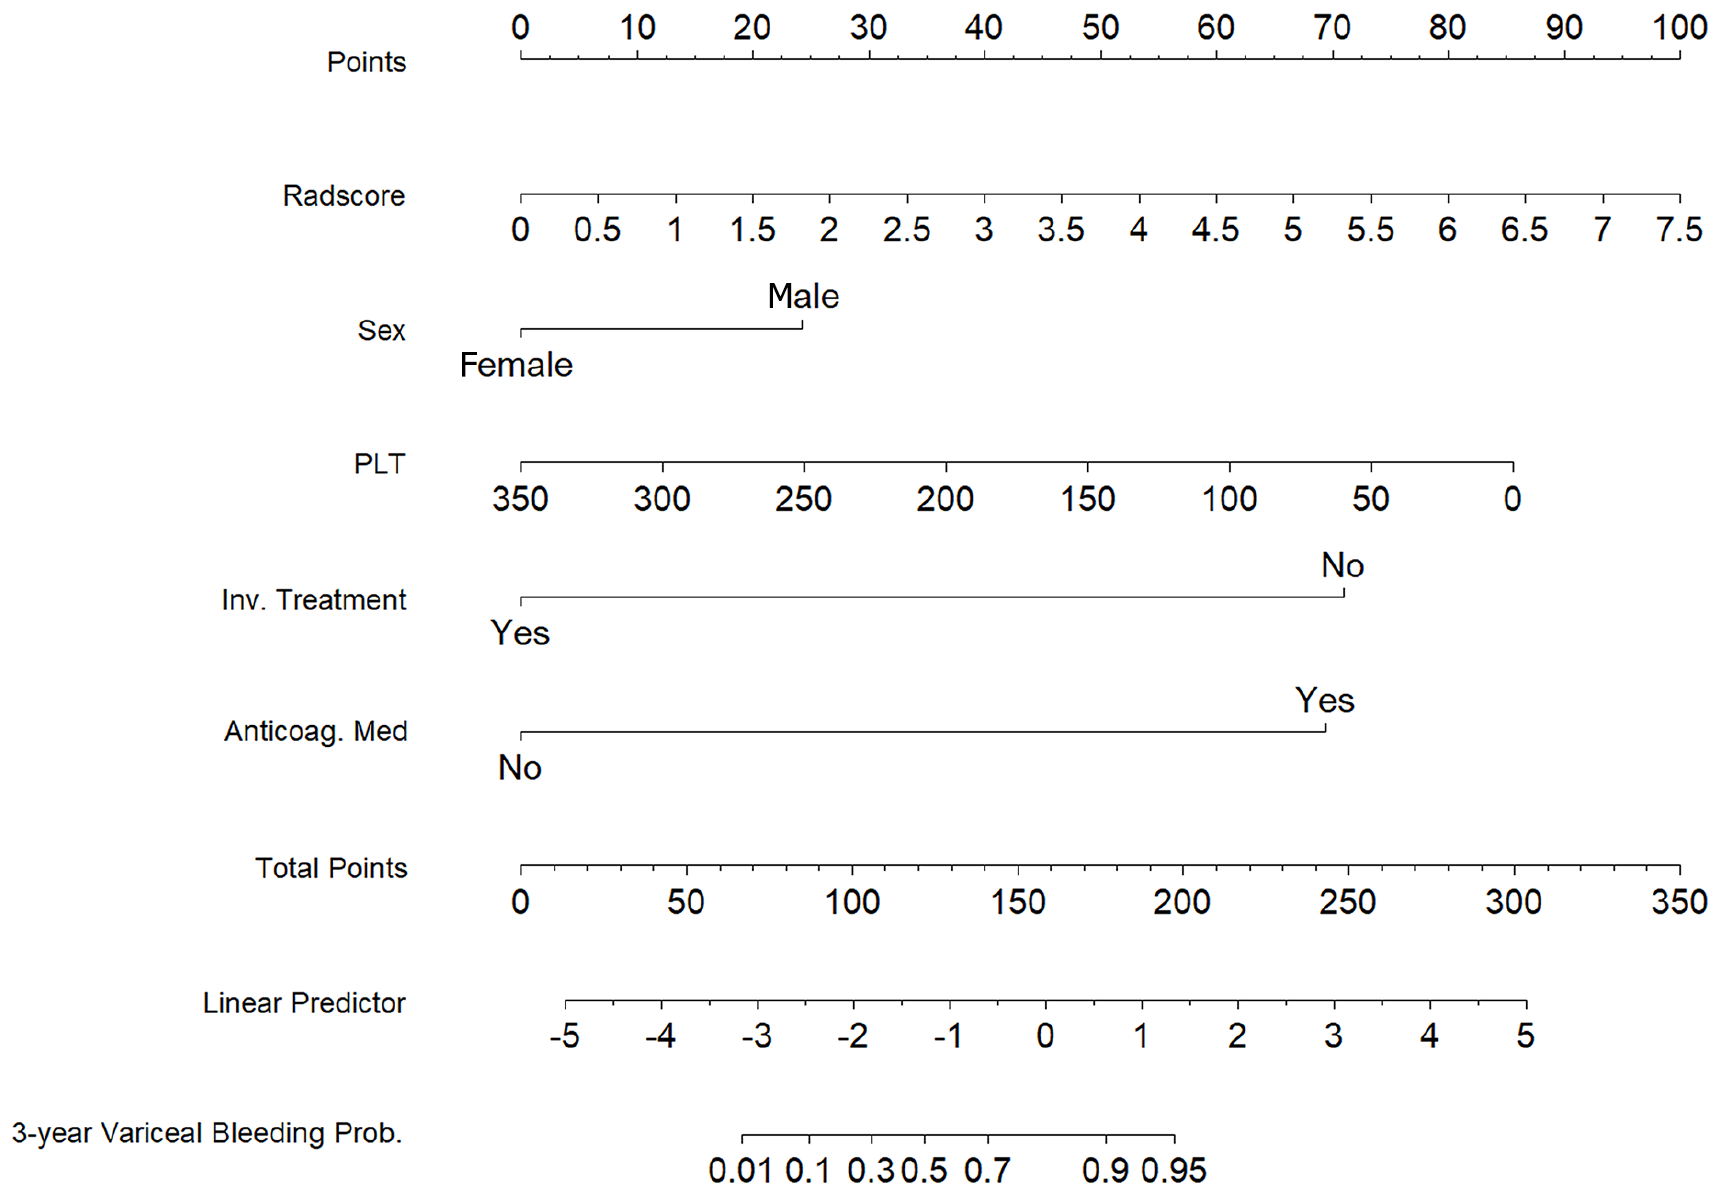

To construct a comprehensive risk prediction model, the radiomics-based Radscore was integrated with significant clinical variables identified through multivariate Cox regression analysis. The final model revealed that the following were independent risk factors for bleeding in patients with BCS. Invasive treatment to relieve hepatic venous outflow obstruction [hazard ratio (HR) = 0.089, 95%CI = 0.044-0.181, P < 0.001), use of anticoagulants (HR = 10.653, 95%CI = 3.102-36.582, P < 0.001), gender (HR = 2.332, 95%CI = 1.057-5.144, P = 0.036), platelet count (HR = 0.992, 95%CI = 0.984-0.999, P = 0.035), and Radscore (HR = 1.545, 95%CI = 1.236-1.932, P < 0.001). These variables were incorporated into a nomogram for individualized prediction (Figure 4). The predictive accuracy of the radiomics + clinical (R + C) model was assessed using the C-index, which achieved values of 0.906 in the training set and 0.859 in the validation set, indicating excellent discrimination. The R + C model demonstrated better predictive performance compared to the clinical-only model (C model) and the radiomics-only model (Radscore; Table 4). ROC curves were generated to assess model discrimination over a 3-year follow-up period. The results showed that the R + C model achieved superior discrimination compared to the individual Radscore and C model, as reflected by its larger AUC in both the training and validation datasets (Figure 5). Calibration curves confirmed a strong alignment between predicted and observed outcomes (Figure 6), while DCA demonstrated the superior net clinical benefit of the R + C model across a wide range of threshold probabilities (Figure 7).

According to the R + C model, the risk analysis was performed for individuals diagnosed with BCS complicated by GEVs. The relevant equation was as follows: Risk assessment = 0.847 Sex - 0.008 platelet count - 2.417 invasive treatment to relieve hepatic venous outflow obstruction + 2.366 use of anticoagulant medication + 0.435 Radscore. The specific threshold was identified through X-tile, and all participants were classified into low-, moderate- or high-risk categories according to their likelihood of bleeding (low risk: < 0.57; medium risk: 0.57-1.11; high risk: > 1.11). In the training set, the cumulative occurrence rates of variceal hemorrhage were 2.2%, 14.7% and 85.3% for the low-, moderate- and high-risk groups, respectively (log-rank test, P < 0.001; Figure 8A). Within the validation group, the cumulative incidence rates were 3.9%, 17.4% and 90% for each group (log-rank test, P < 0.001; Figure 8B), which suggests that the model effectively differentiated the risk of variceal bleeding in patients with BCS complicated by GEVs.